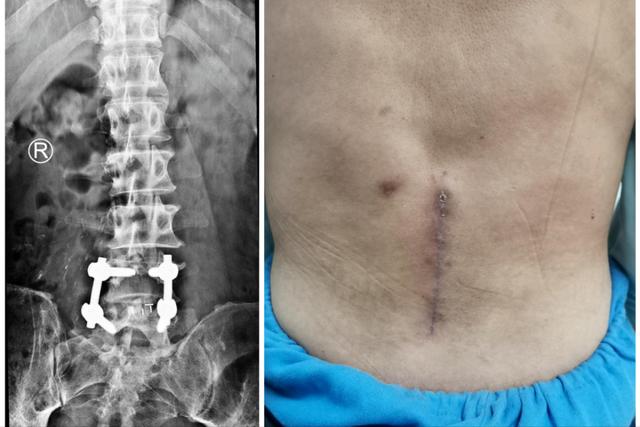

在治疗上我们一般分为两步,前中期我们采取保守治疗,通过物理疗法,也就是理疗之类的,在配合中药内服外敷进行调理,大多数腰间盘突出的患者都能慢慢的改善。如果到了后期,或者说保守治疗之后病情没有得到改善的时候,这时候可能出现大小便失禁等严重情况,我们需要考虑手术治疗,在手术治疗上我也有这很多年的手术经验。当然我们要尽量避免拖到后期,做好前中期的预防工作和积极的检查治疗,不要让腰间盘突出影响自己的生活。

腰间盘突出晚期患者手术治疗